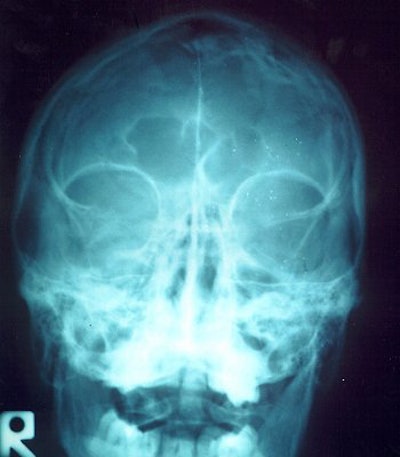

![]() |

| If the frontal sinuses (above) of an unidentified corpse are intact, they can be as distinctive as fingerprints. Bone spurs (below) can also be unique identifying markers, as these two example x-rays show. Images courtesy of Nancy Adams. |

Adams offered some details on how forensics experts apply imaging to body identification. Frontal sinuses "can be as unique as fingerprints," she said. "You also do the feet. There will be bone spurs on the heels. Another thing is the legs. One individual had a total knee replacement."